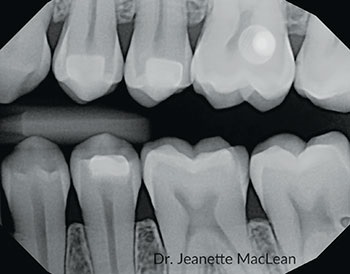

Fig. 5: A 19-year-old male with incipient proximal caries lesion on the distal of the mandibular left first permanent molar.

Fig. 7: A six-month follow-up bitewing shows the distal lesion on the mandibular left first permanent molar has not cavitated.